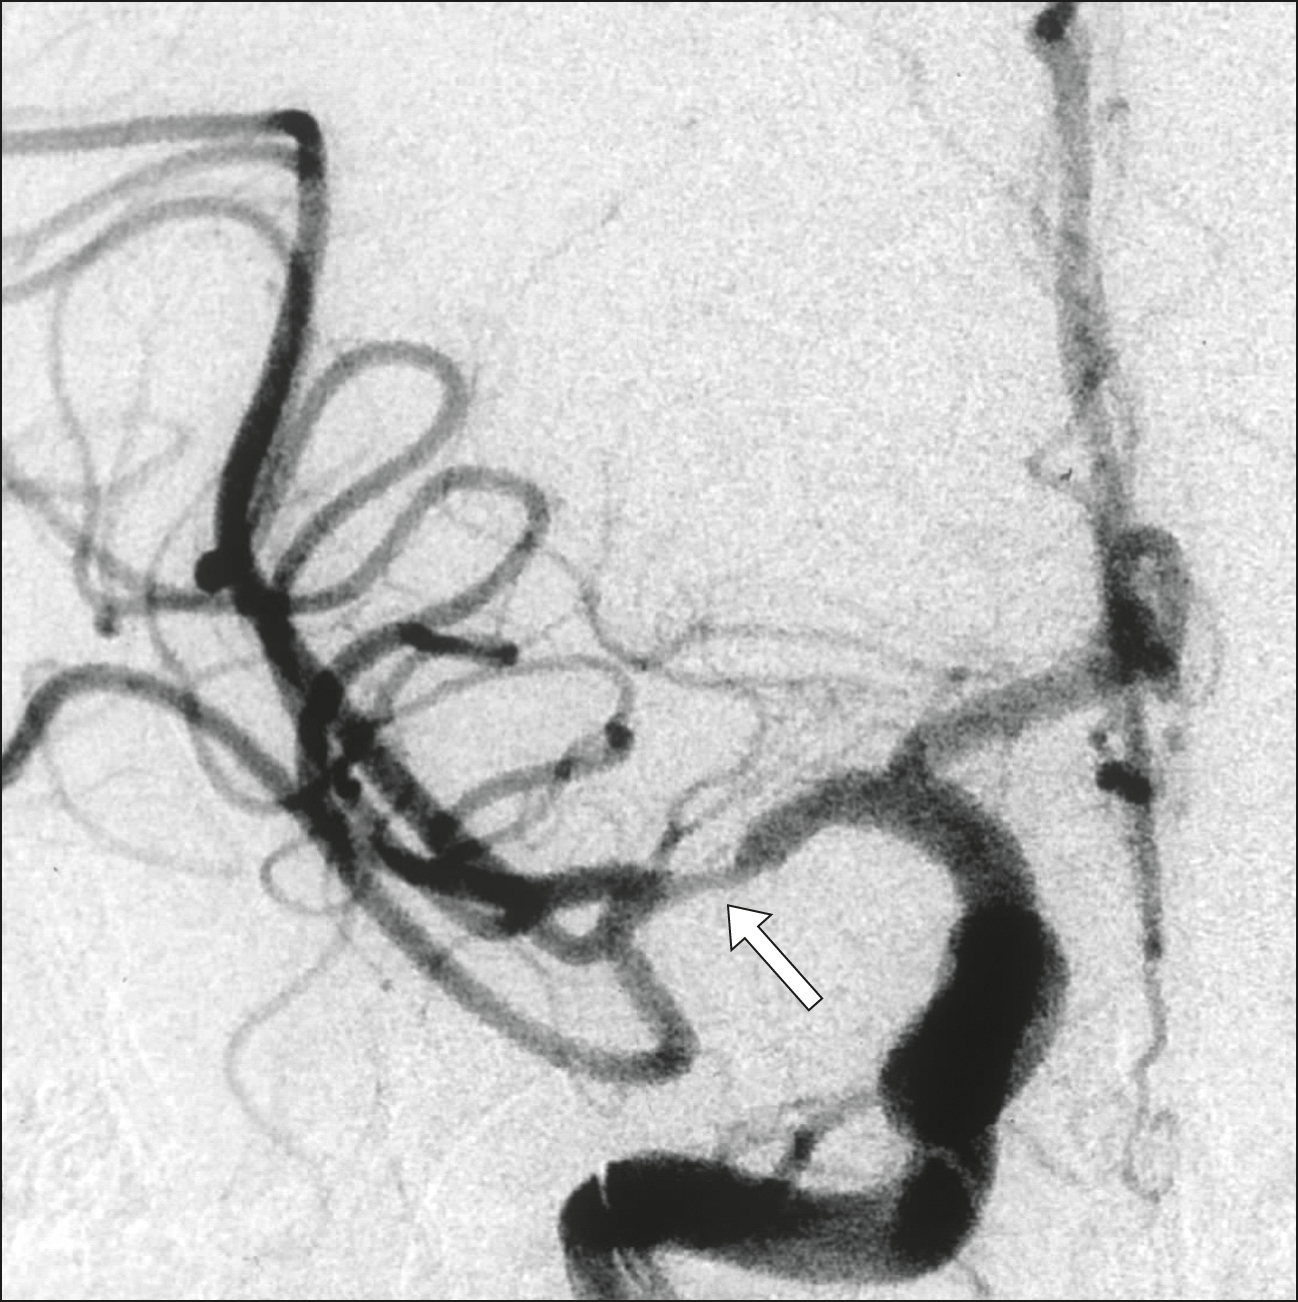

Terapia endovascular del ACV: cómo son los resultados en la vida real

09 abril 2018

El registro nacional holandés de las intervenciones para el tratamiento inicial del ACV isquémico muestra resultados comparables a los obtenidos en los ensayos clínicos. BMJ, marzo de 2018